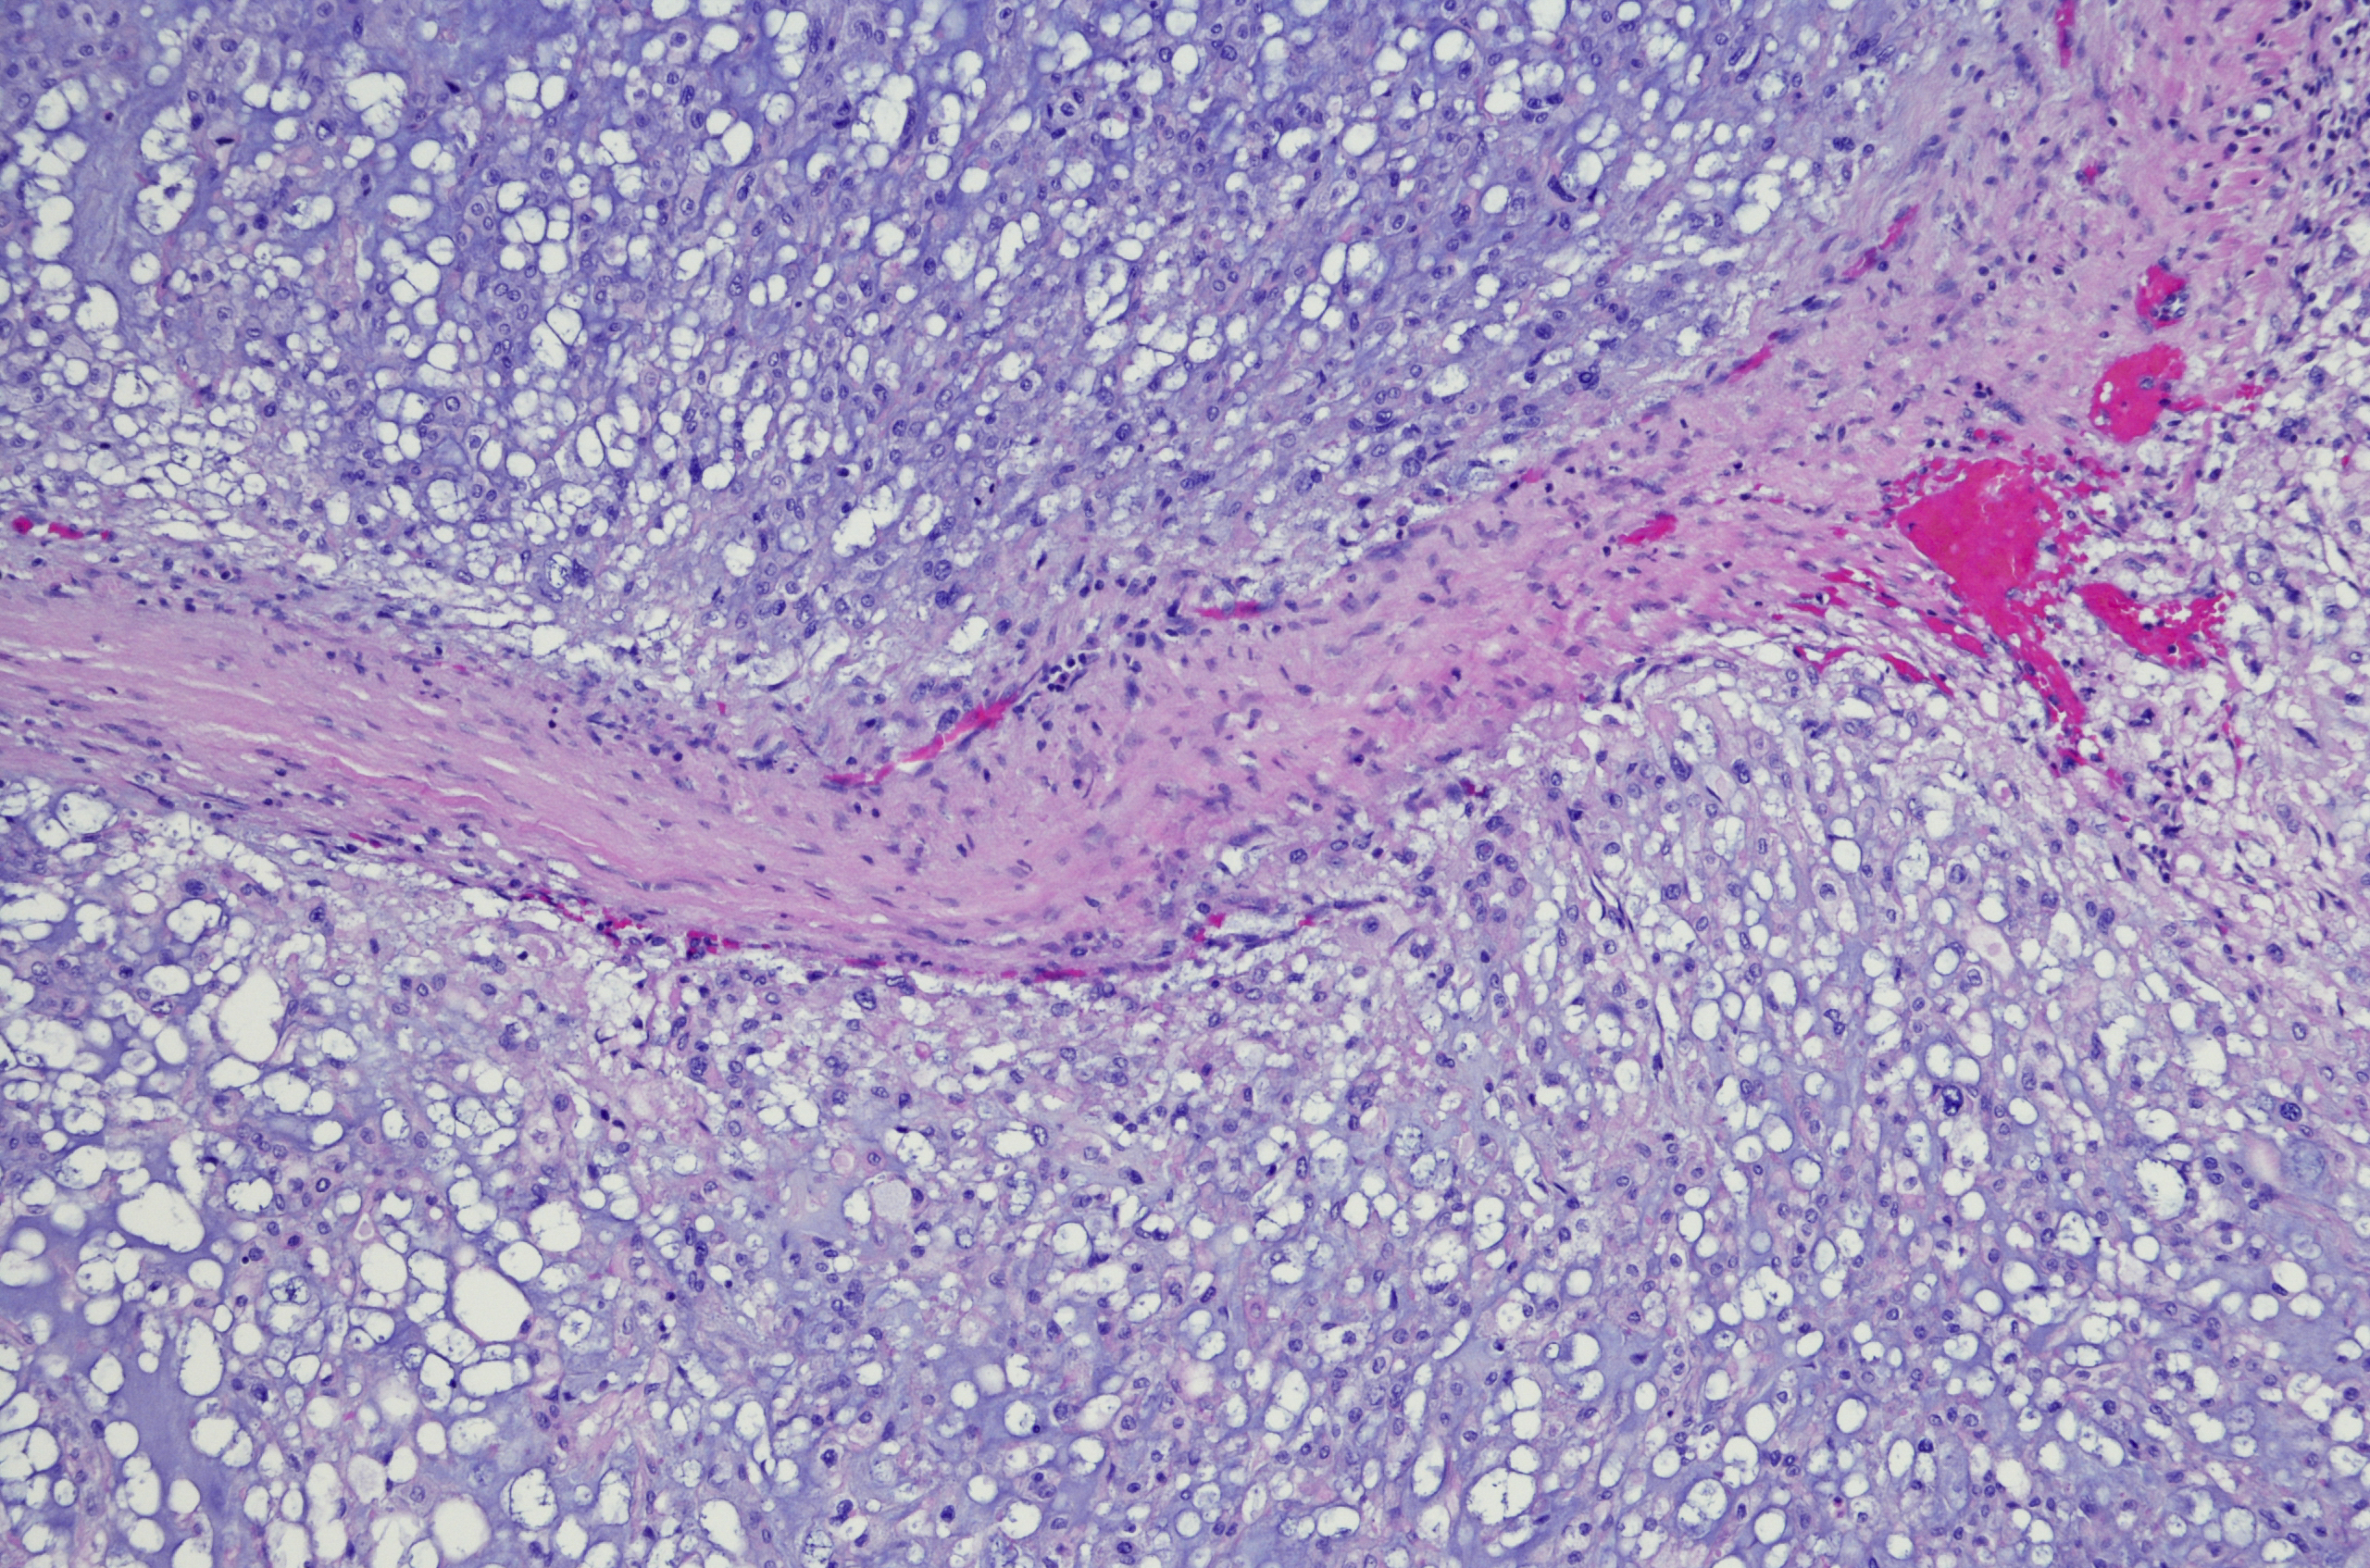

A Chordoma is a rare type of cancer that develops from the notochord. The notochord forms the spine in a foetus and, usually after around six months, most of the notochord is replaced by vertebrae. However, small amounts of the notochord may remain and these can sometimes develop into a chordoma, which can occur at any age.